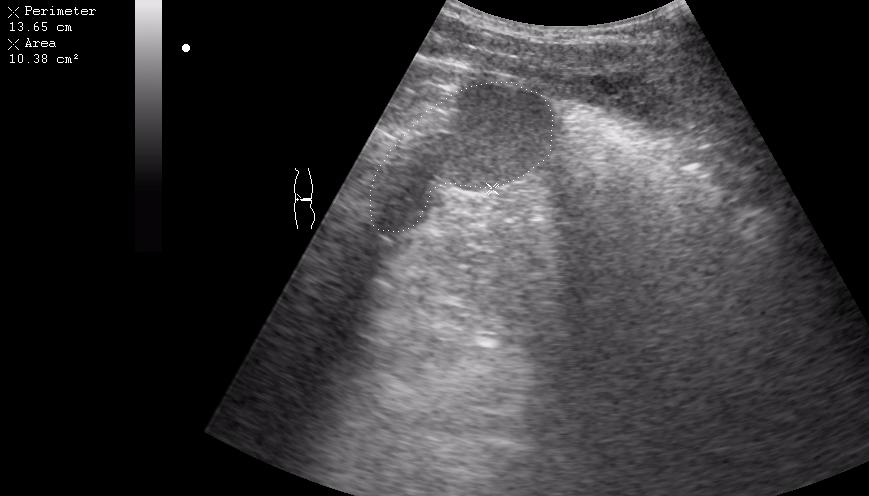

Девочка-подросток поступила в приемное отделение с жалобами на боли в эпигастральной области. На животе - рубец после срединной лапоротомии - полгода назад оперирована по поводу травмы и разрыва селезенки, со слов мамы - выполнена спленэктомия.

При УЗИ в эпигастральной области обнаружилось такое образование.

Да, действительно, это аутотрансплантат ткани селезенки в большой сальник.